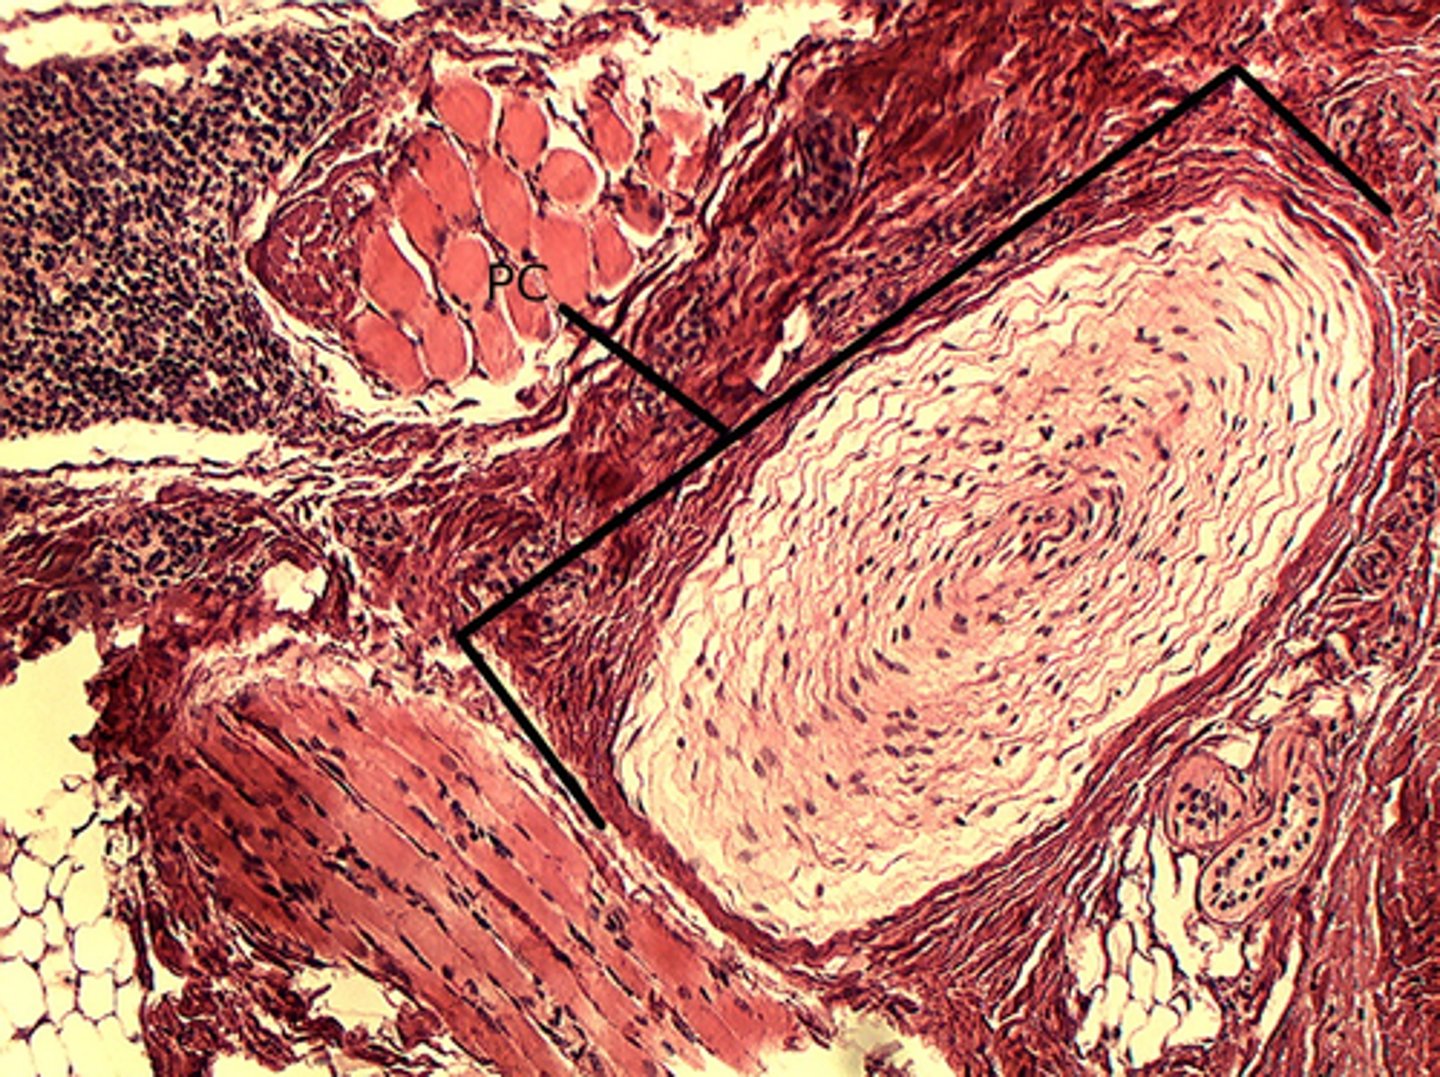

Lamellated corpuscles (Pacinian corpuscles)

what is this called?

<p>what is this called?</p>

12

New cards

Lamellated (Pacinian) corpuscles

what is the structure in the bracket called?

<p>what is the structure in the bracket called?</p>

13

What is the red arrow pointing to?

<p>What is the red arrow pointing to?</p>